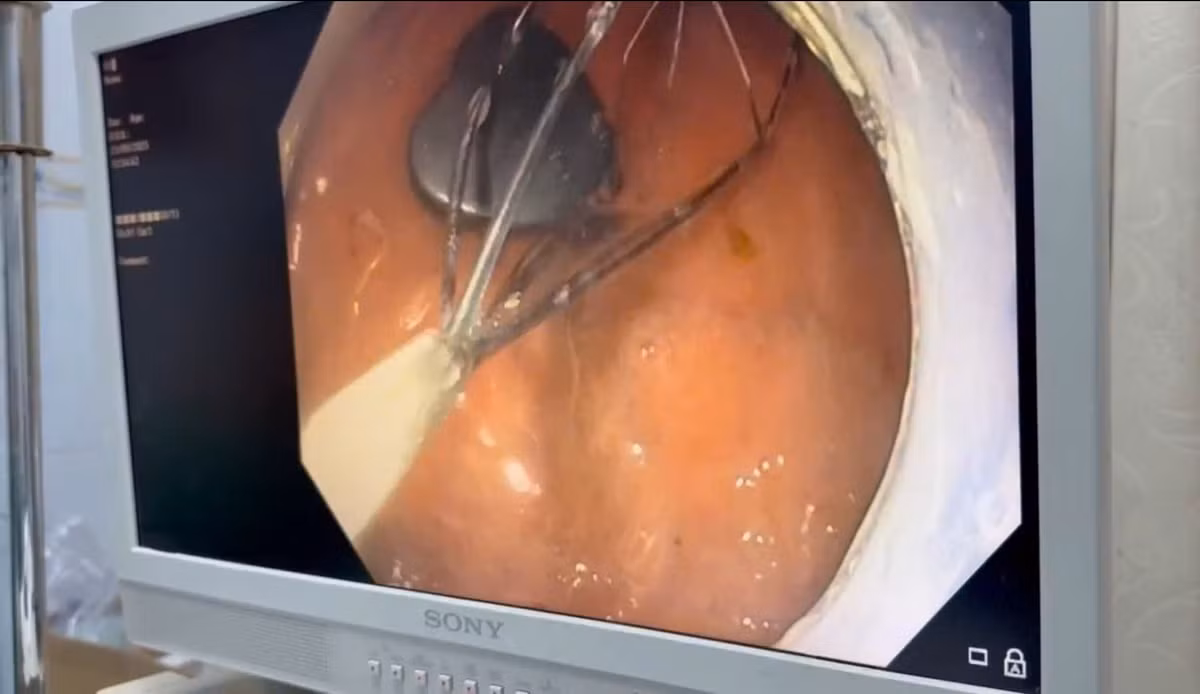

Ngay lập tức, bệnh nhi được chuyển đến Khoa Nội soi. Ê-kíp bác sĩ tiến hành nội soi gây mê, sử dụng dụng cụ chuyên dụng để gắp dị vật. Sau một khoảng thời gian ngắn, cục nam châm đã được lấy ra an toàn. Kiểm tra đường tiêu hóa không ghi nhận tổn thương, bé tỉnh táo và được xuất viện trong ngày.

Nội soi lấy nam châm hình trái tim trong dạ dày bệnh nhi - Ảnh BVCC